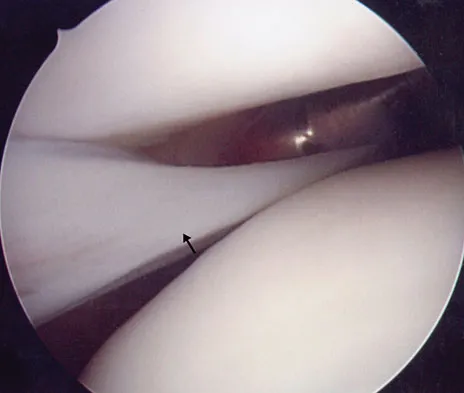

Figure 42 shows the sagittal T2-weighted MRI scan of a patient's right knee. These findings are most commonly seen with a complete tear of the

The MRI scan reveals disruption of the lateral capsule and ligaments with fluid in the soft tissues laterally. Additionally, there is a large bone bruise on the medial femoral condyle. This combination indicates injury to the posterolateral complex. These injuries often have coexisting anterior and/or posterior cruciate ligament injuries. Failure to recognize the posterolateral corner injury can lead to failure of anterior or posterior cruciate ligament reconstructions. LaPrade RF, Gilbert TJ, Bollom TS, et al: The magnetic resonance imaging appearance of individual structures of the posterolateral knee: A prospective study of normal knees and knees with surgically verified grade III injuries. Am J Sports Med 2000;28:191-199.